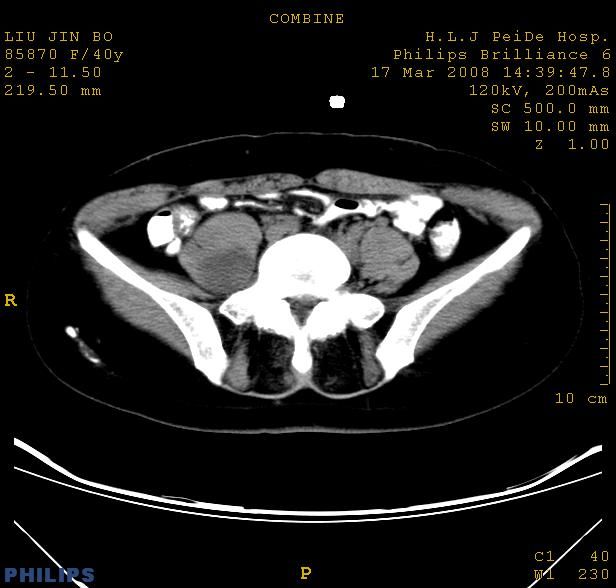

以下是引用qiuleiyu在2008-4-27 12:36:00的发言:[br]支持;右侧腰大肌后方神经源性肿瘤可能大,神经节细胞瘤?

以下是引用形影不离在2008-4-27 14:11:00的发言:[br]1.考虑右侧腰大肌脓肿。[br]2.左侧附件区炎症。[br]3.子宫增大,建议:进一步检查。